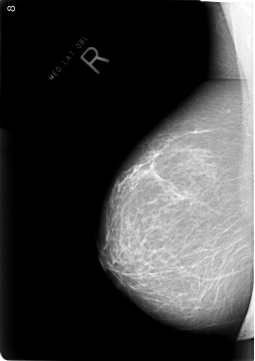

B_3017_1.RIGHT_CC

RIGHT_CC LINES 5752 PIXELS_PER_LINE 4056 BITS_PER_PIXEL 12 RESOLUTION 50 NON_OVERLAY